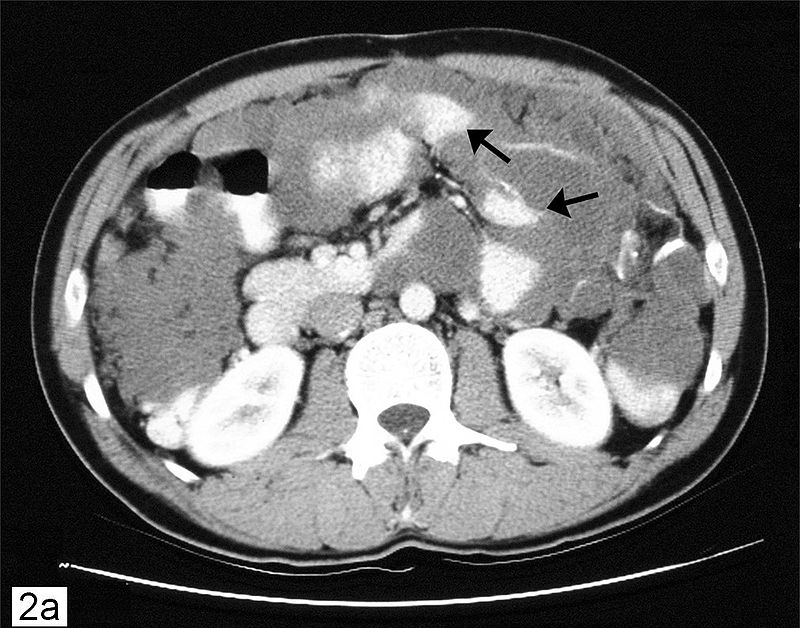

The most common cause of the metastatic mucinous Krukenberg tumor, which affects both ovaries, is metastatic gastric carcinoma (diffuse type).

Bilaterality helps distinguish metastases from primary mucinous carcinoma of the ovary (primary mucinous carcinoma is usually unilateral).